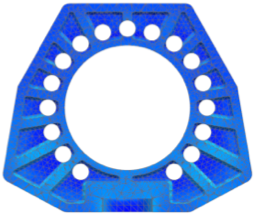

Obr. 1 Topologicky optimalizovaný dizajn implantátu vyrobý z materiálu PEEK (vľavo), z materiálu Ti (vpravo)